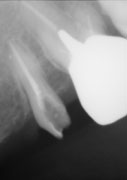

虫歯はじっとしていても痛むような大きさになると、虫歯菌が歯の神経の中に入ってしまい、神経をとらないと痛みが取れません。ところが神経をとった歯の空洞で細菌が繁殖すると人間の免疫力が働かないため、細菌はどんどん増殖して、化膿して「歯が浮いて痛くて噛めない」という状態になります。したがって、細菌が繁殖しないように細菌の繁殖元となる死んだ神経をきれいに取り、細菌の住める空洞をなくすために、緊密に神経をとった根の穴を埋める必要があります。しかしながら、歯の神経の形態は複雑で、時に湾曲したり、枝別れしたりしています(図1)。

図1